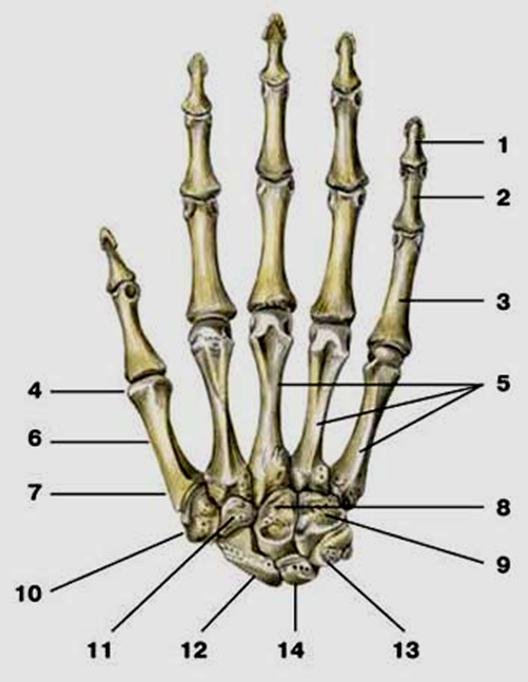

S: Числом 10 обозначена os ### (латинский язык).

S: Цифра 5 обозначает ossa ### (латинский язык).

S: Цифрой 8 обозначена os...

S: Числом 12 обозначена os...

S: Числом 13 обозначена os...

S: Цифра 3 указывает на...

S: Цифра 2 указывает на …

S: Цифра 1 указывает на....